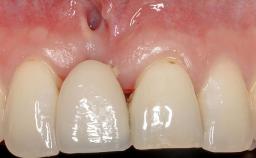

Adequate peri-implant soft-tissue thickness is essential not only for esthetic but also for functional reasons. In this case, Vincenzo Iorio Siciliano demonstrates how he achieved increased height and thickness of posterior peri-implant soft tissues to obtain a stable mucosal seal and a width of keratinized tissue favorable to toothbrushing.

The patient, a healthy 38-year-old woman, was referred for increasing the width of the keratinized tissues at the buccal aspect of dental implant 46. The site exhibited a premature-closure screw exposure caused by trauma during chewing, with inadequate keratinized tissue.